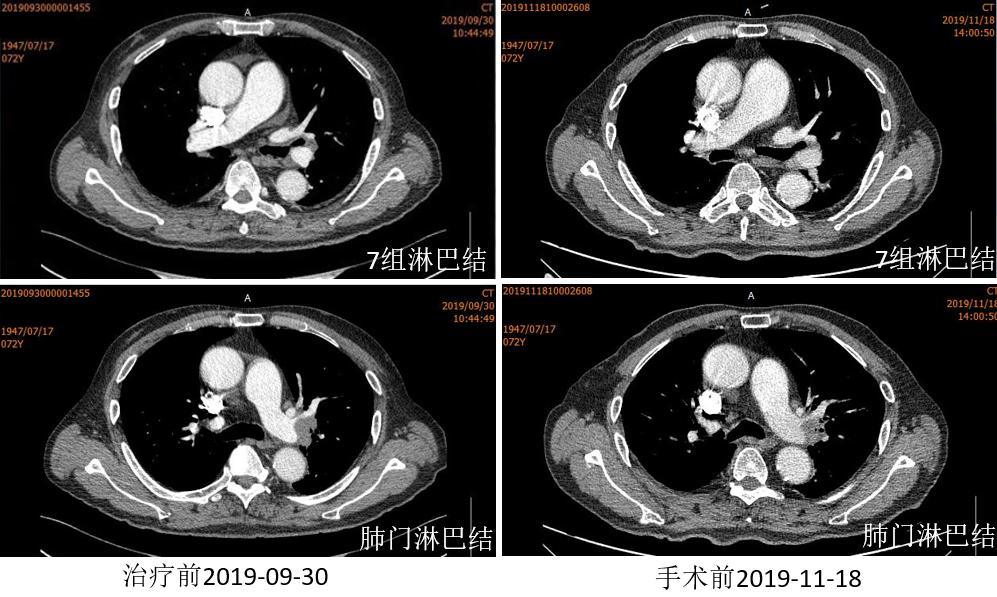

胸部CT

2019.12.03 行“VATS辅助切口左肺上叶袖式切除术”。

术后病理:(左上叶)未见肿瘤细胞残留。病灶内大片区域纤维化伴胶原化,组织细胞积聚,淋巴细胞浸润,病灶周边见个别多核巨细胞反应,符合化疗后表现(疗效PCR)。第6、7组淋巴结见钙化灶,未见癌细胞。肺门支气管旁淋巴结未见癌细胞,见纤维组织增生伴胶原化及黑色颗粒沉积。

疗效评价:pCR(病理完全缓解:原发灶和淋巴结手术标本病理检查无浸润性肿瘤细胞残余)。